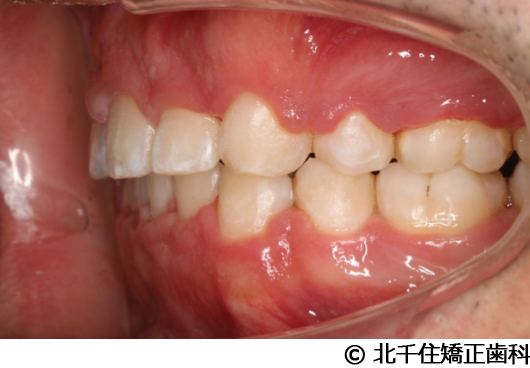

【症例5】上顎前突

- 治療前

- 治療後

- 治療名

- 上顎前突

- 費用

- 1,263,600円(税込)

- 期間

- 2年8ヵ月

- 治療回数

- 32回

- 通院頻度

- 1ヵ月ごと

- 年齢

- 13歳3ヵ月(初診時)

治療内容

-

患者様の症状

主訴:出っ歯

治療方法

骨格性の上顎前突、ヘッドギアを併用して上下顎第一小臼歯4本抜歯してワイヤー矯正。

治療結果

骨格性上顎前突に対し、ヘッドギアおよび抜歯を併用した矯正治療により歯列および咬合関係の調整を行った症例である。

治療後は保定装置を使用し、歯列および咬合の安定維持を目的として定期的な経過観察を行っている。

※治療結果は個人差があります。

治療を行う上での注意点(リスク・副作用)

歯磨き不良に伴うカリエスや歯周病、歯根吸収など。